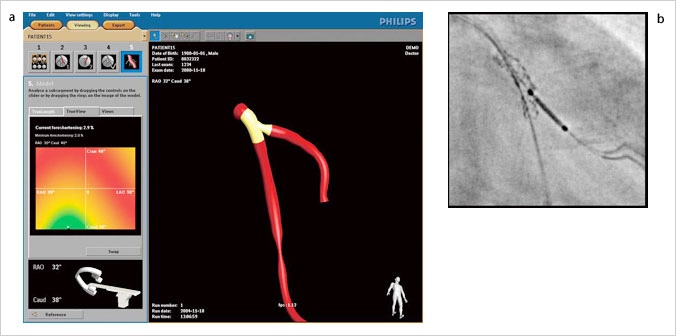

心臓CTの進歩は目覚ましく,現在では多くの施設で活用されている。心臓CTでは,高精細な3D画像が生成され,これらは複雑なPCI時に多用され始めている。フィリップスでは,心臓CTデータを利用し最適なアプローチアングルをシミュレートして,目的のワーキングアングルへのオートポジションを実現する“CT TrueView”を開発した。このアプリケーションソフトウェア上で術者は,選択病変部の最適なアングルを選択することができる。また,Optimal View Map機能により,臨床角度を装置側が自動計算し提示する(図3)。

図3 CT TrueView